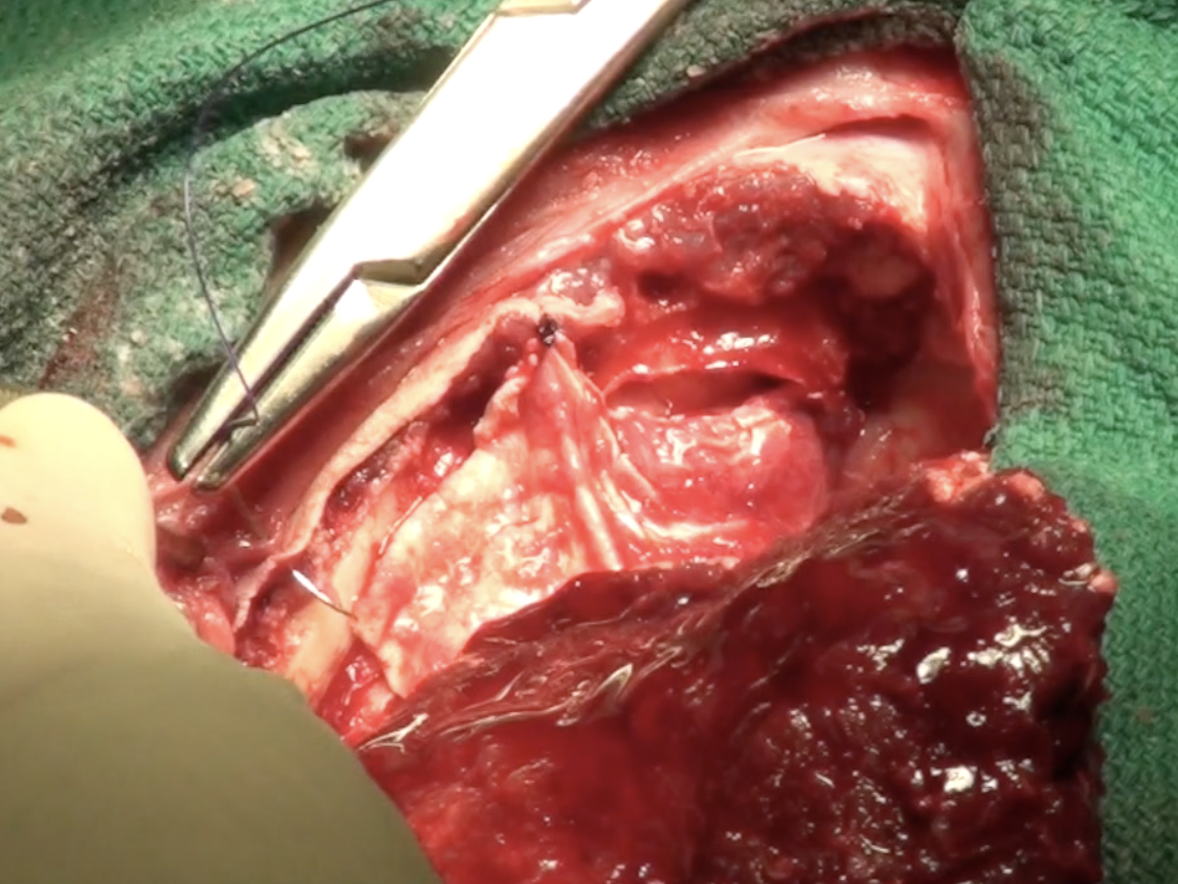

The temporalis fascia can be harvested as a dural replacement. This graft can be used over exposed brain (where the dura has been removed) and similarly in the spinal cord to protect the neural tissue from overlying muscle (where fibroblasts migrate from). Often used when other grafting material is not available or to save money (it’s free!). In this short video, Sean Sanders describes the technique.